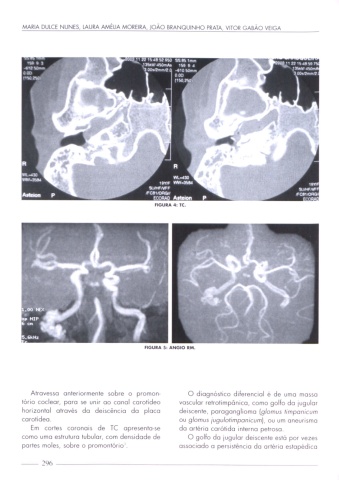

FIGURA 4: 1C.

FIGURA 5: ANGIO RM.

Atrovesso anteriormente sobre o promon- O diagnóstico diferencial é de umo mosso

tório cocleor, para se unir oo conol corotideo vascular relrotimponico, como golfo do lugulor

horizontal através do deiscéncio do ploco deisceme, porogongliomo (glomus r/mponicum

corotideo. ou glomus jugu/ofimpanicum), ou um oneunsmo

Em cortes coronois de TC opresentose

do orlério carótida interno penoso.

como umo estrutura tubular, com densidade de

O golfo do jugular deiscente está por vezes

portes moles, sobre o promontório _

ossociodo o persistência do ortério estopédlco